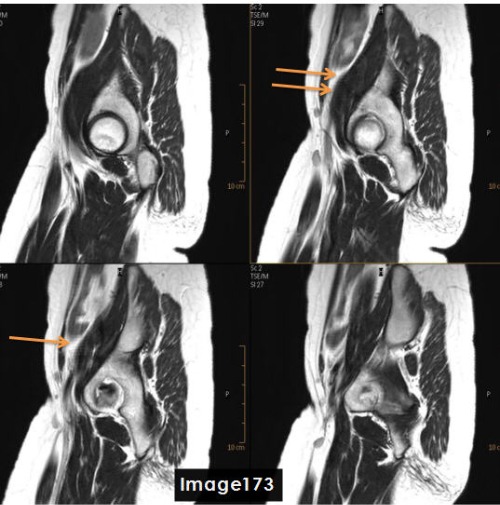

The artifact identified by the orange arrows in Image 173 is a ________ artifact.

A. Chemical shift

B. FID crushing / fine line

C. Dielectric effects

D. Wraparound (aliasing)

To correct for the fine line artifact shown in Image 173, which can be caused by unstable FID signals, the MRI Technologist would:

A. Increase NEX

B. Decrease NEX

C. Enable Flow Compensation

D. A or C

D. A or C (Increase NEX or Enable Flow Compensation)